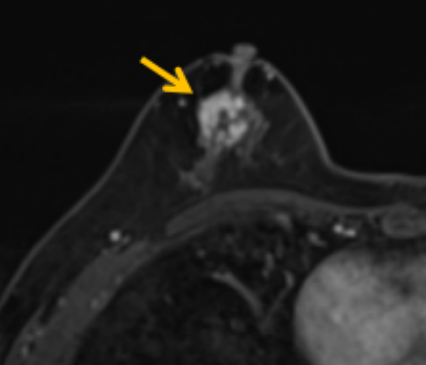

陳寶瑩評(píng)估圖像后發(fā)現(xiàn)病變?yōu)閮H僅在磁共振增強(qiáng)時(shí)顯示,為非腫塊樣病變,比較散,必須取得足夠多的組織才能確保病理檢查的準(zhǔn)確性,常用的核芯針活檢獲取的組織較少,因此最終確定了磁共振引導(dǎo)下行真空輔助抽吸旋切活檢。取得患者及家屬認(rèn)可后,陳寶瑩帶領(lǐng)團(tuán)隊(duì)開始進(jìn)行術(shù)前準(zhǔn)備。

針對(duì)患者乳房小固定難度大這一問(wèn)題,陳寶瑩通過(guò)巧妙體位和固定器的調(diào)整,順利固定好乳房。經(jīng)過(guò)磁共振多模態(tài)掃描,陳寶瑩找出病變活性成分相對(duì)集中區(qū)域,精準(zhǔn)確定穿刺路徑,置入引導(dǎo)針、旋切針,到位后多角度旋切取出足量組織,拔除旋切針后即時(shí)行磁共振掃描,精準(zhǔn)取得組織且術(shù)區(qū)出血很少,遂加壓包扎,整個(gè)過(guò)程非常順利,旋切活檢后患者回家休息。兩天后隨訪,李女士沒(méi)有任何不適,五天后皮膚上幾毫米的小切口已經(jīng)愈合。最終病理結(jié)果證實(shí)為乳腺導(dǎo)管原位癌,為早期乳腺癌,為患者后續(xù)針對(duì)性治療奠定了基礎(chǔ)。